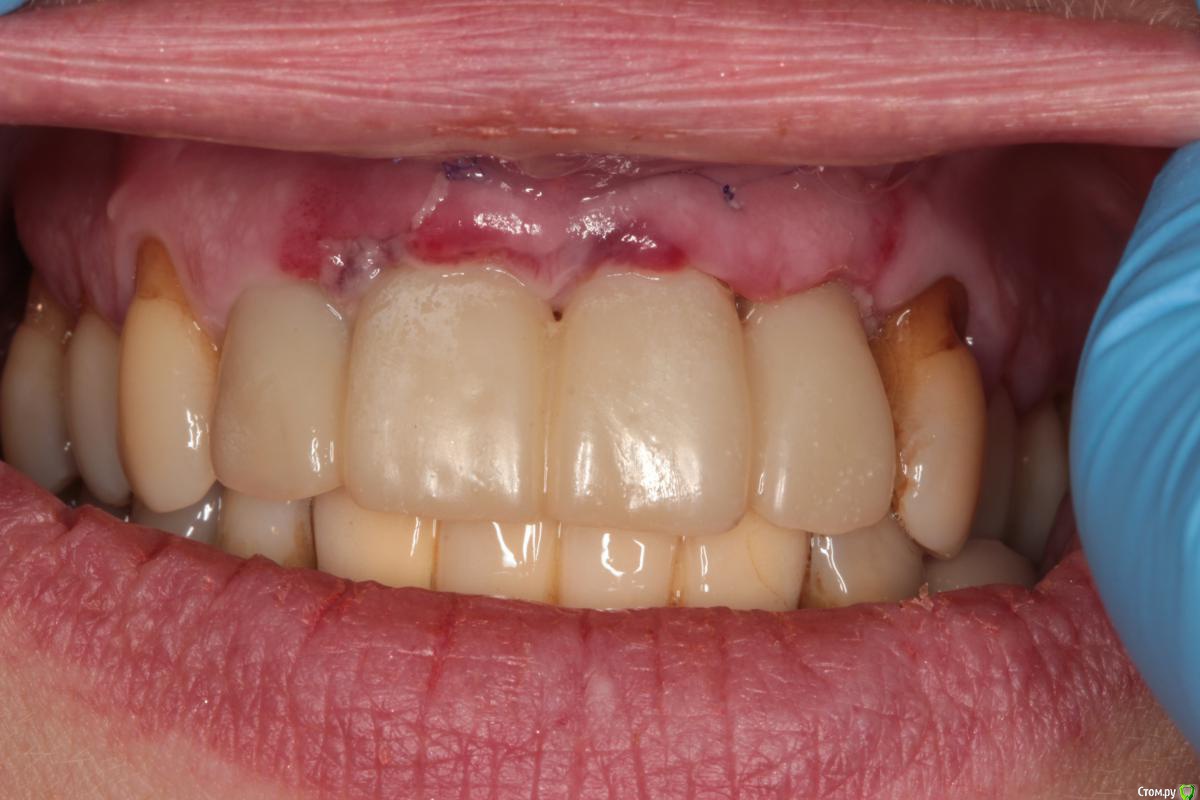

Abuk Опубликовано 27 ноября, 2015 Поделиться Опубликовано 27 ноября, 2015 (изменено) 1.bmp2.bmp3.bmp4.bmpЛечение.Альгинатные слепки,восковая моделировка.Удаление зубов и имплантата,удаление грануляций.Установка имплантатов,заполнение лунок графтом.сст,Времяхи по ключу. Изменено 27 ноября, 2015 пользователем Abuk 13 Ссылка на комментарий

Abuk Опубликовано 29 ноября, 2015 Автор Поделиться Опубликовано 29 ноября, 2015 (изменено) 1 е фото -"до", после были слепки и гигиена.Непосредственно перед имплантацией нет.Гигиена не фонтан,условились на том что первый год приходит каждые 3 месяца(осмотр и ггигиена),а там далее смотрим. Изменено 29 ноября, 2015 пользователем Abuk Ссылка на комментарий